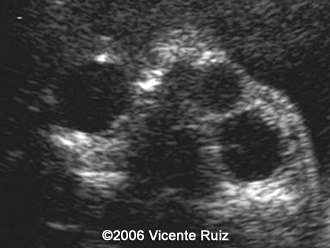

Dacryocystocele

Vicente Jesus Ruiz, MD

Centro de Ecografia Dr. Vicente J Ruiz, Salta, Argentina

This is a case of dacryocystocele in a third  trimester fetus. Note the cystic mass between the right medial cantus and the nose.